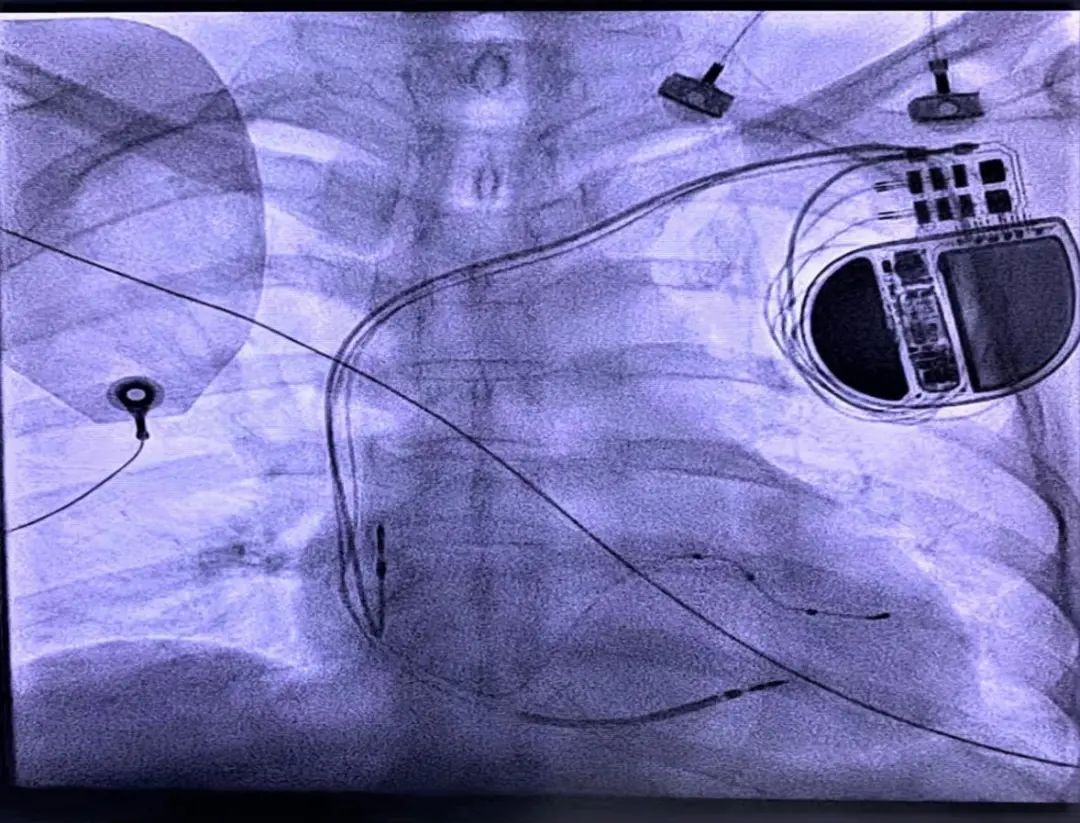

不過,這個顧慮很快就被打消,因為醫(yī)院有Rivacor 7 HF-T的CRT-D。

不僅可以兼容全身自動核磁共振,而且具有左室多部位起搏功能。它不僅在關(guān)鍵時候能救命,還具有逆轉(zhuǎn)心室重構(gòu),治療心衰。

11月20號,在李衛(wèi)華書記、謝強副院長和唐蓉主任率領(lǐng)下,馬欲曉主任醫(yī)師等心內(nèi)科起搏團隊經(jīng)過充分術(shù)前準備,開始手術(shù)。

術(shù)中發(fā)現(xiàn)患者多條靶血管及多位點均出現(xiàn)高閾值,提示左室心肌彌漫性纖維化。

慶幸的是,該CRT-D配套左室四級電極有20種向量匹配,經(jīng)過參數(shù)優(yōu)化,最終篩選出滿意起搏位點和參數(shù)。

術(shù)后,開啟了CRT AutoAdapt功能,通過單左室起搏和右室自身下傳激動形成融合,QRS波由術(shù)前187ms縮短至130ms,提示左右心室不同步的情況得到明顯改善。

心臟再同步化治療心臟自動除顫器簡稱CRT-D,具有心臟再同步化(CRT)治療和心臟自動除顫器(ICD)的雙重功能。CRT是通過植入左心室電極,使左右心室同步化收縮,使擴大的心臟逐漸縮小,能顯著改善心臟功能,延緩患者心衰的進展。而ICD能對惡性心律失常進行除顫,能有效地預(yù)防心源性猝死。